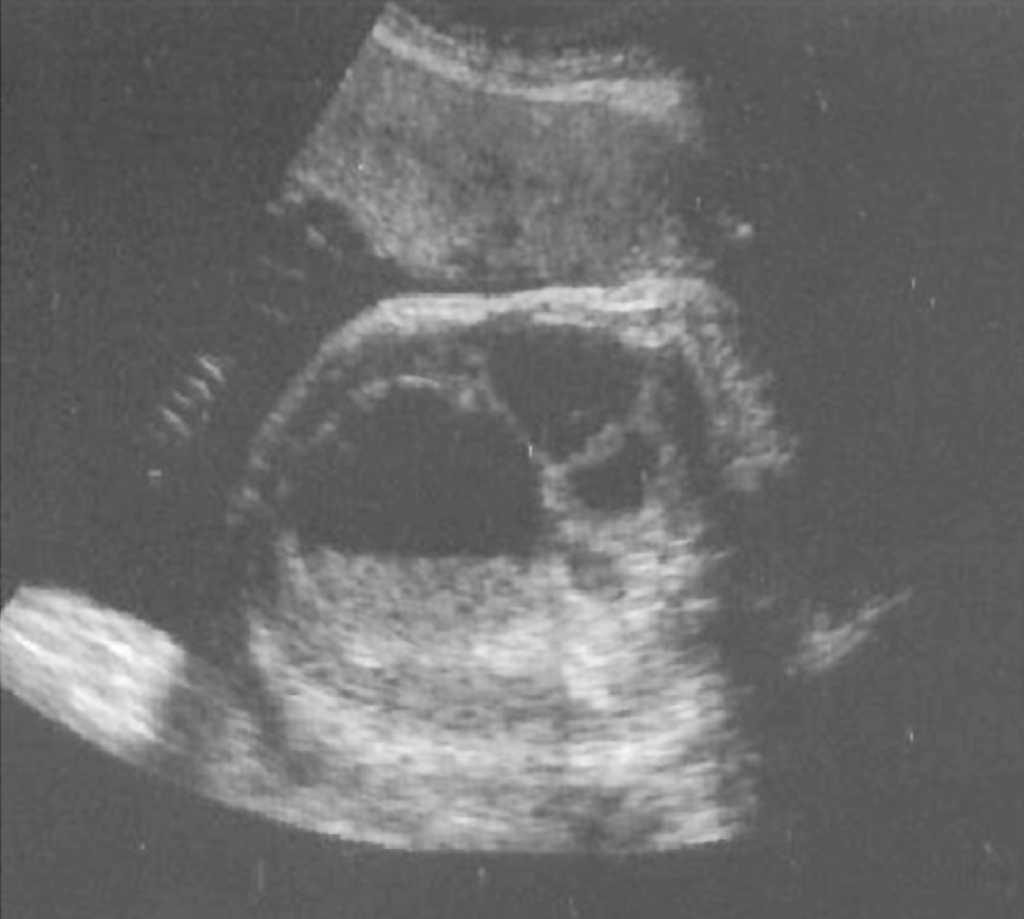

En un primer estudio ecográfico, practicado en la semana 32 + 2, destaca un circunferencia abdominal fetal (CAF) mayor al percentil 95 y un polihidramnios con índice de líquido amniótico (ILA) de 23. En el hemiabdomen inferior se visualiza una tumoración redondeada de aspecto quístico, desde la vejiga al borde hepático, de 59 x 48 x 46 mm de diámetro, con nivel líquido-sólido, compatible con quiste ovárico fetal, con parte sólida avascular (figs. 1 y 2). Las asas intestinales distales se encontraban dilatadas, con peristaltismo y rechazadas en hemiabdomen izquierdo probablemente por compresión extrínseca (fig. 3). No se visualiza líquido libre ni calcificaciones. El resto de la exploración ecográfica se encontraba dentro de la normalidad.

Figura 3.Corte sagital del abdomen fetal con asas intestinales dilatadas en íntimo contacto con estructura quística.

En un segundo estudio ecográfico, realizado en la semana 34 + 2, se aprecia en el hemiabdomen izquierdo y de predominio caudal la formación quística anteriormente descrita, además de múltiples imágenes de contornos bien delimitados con niveles sólido-líquido, que se comunican entres sí, con presencia de peristaltismo. Presentaba un hidramnios de 44 mm y el resto de la anatomía fetal no presentaba otros hallazgos patológicos.

En ese momento se sospecha como causa más probable una atresia de íleon proximal o de yeyuno, apoyado en la presencia de polihidramnios y la dilatación de las asas con contenido líquido localizada en la pelvis fetal (que indica un origen distal).